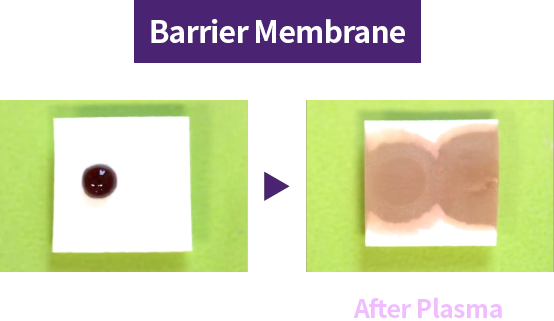

During manufacturing, shipping, and long-term storage, hydrocarbons can accumulate on the implant surface, reducing biocompatibility. Plasma implants remove hydrocarbons with high-energy plasma and reactivate the surface for higher biocompatibility.

Plasma treatment improves surface hydrophilicity → promotes blood and protein adhesion → an implant the body accepts more easily

Plasma treatment helps remove impurities left on the implant surface and improves surface hydrophilicity for better biocompatibility. Thanks to these benefits, plasma technology helps improve implant success and serves as a key factor for faster recovery.

Creating a safer implant surface through removal of surface impurities

Improved early protein attachment through organic removal and surface activation